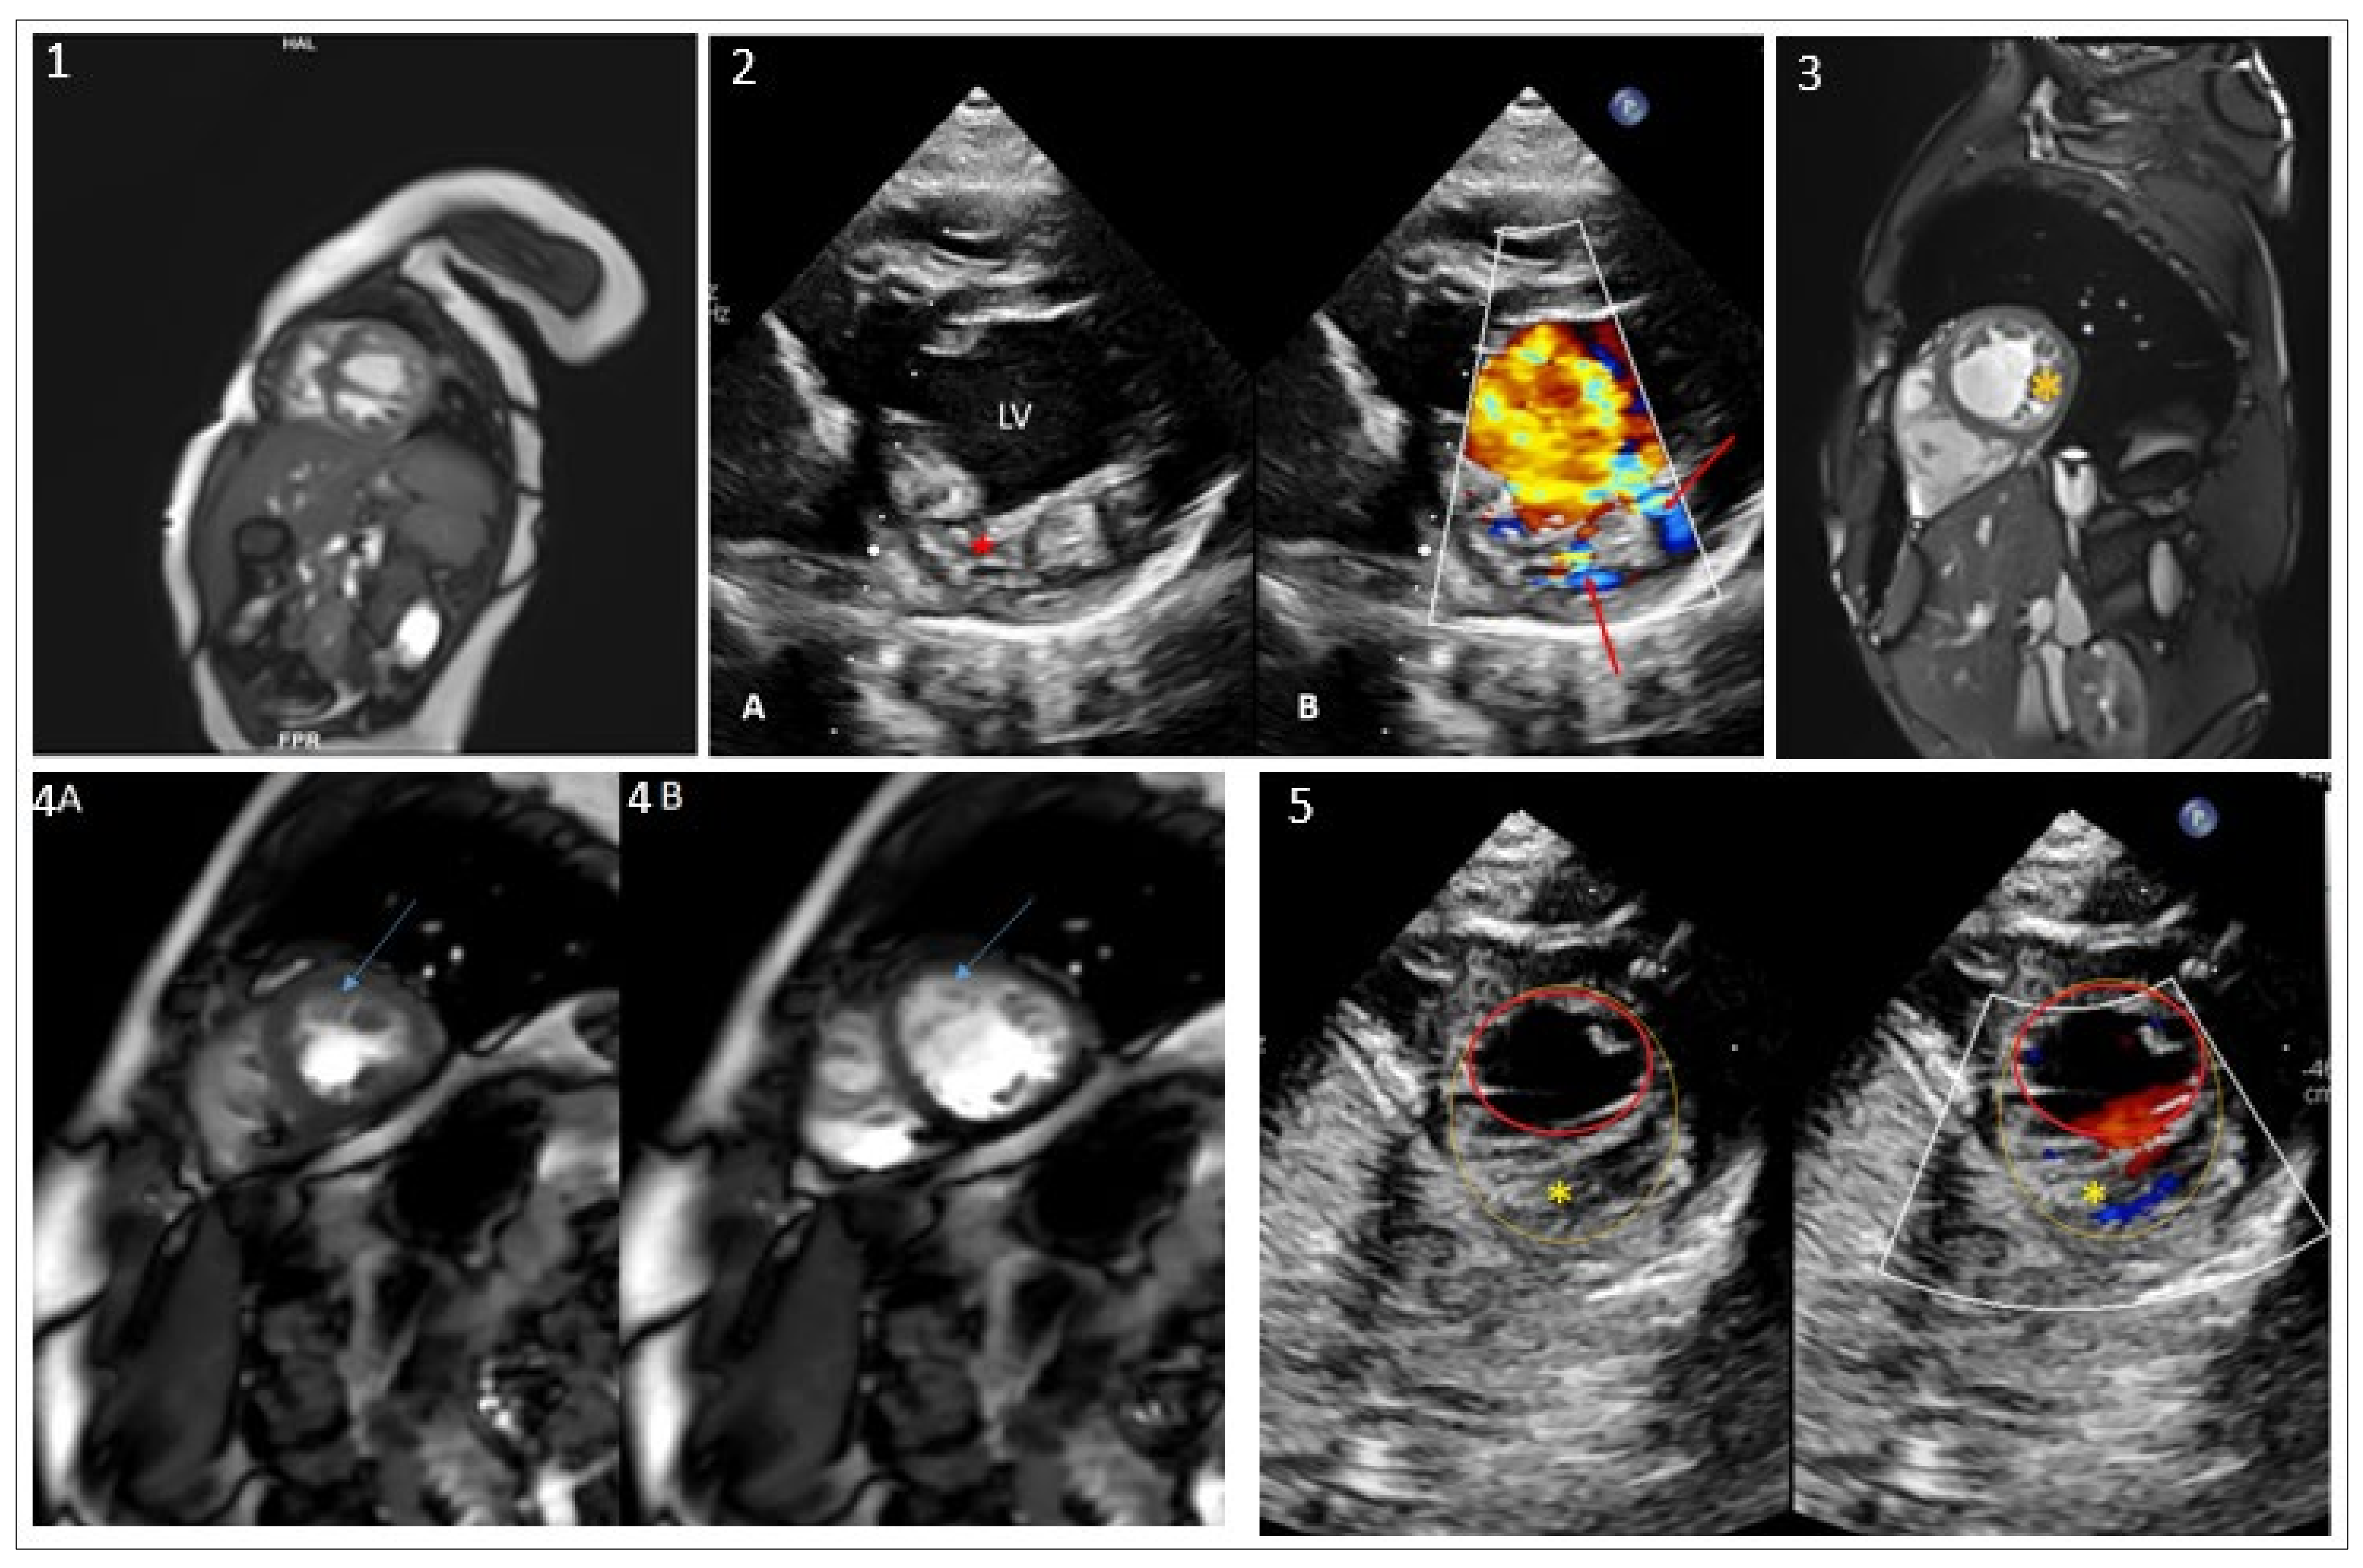

| SPEG | c.7408C>A; c.8059C>A | Arg2470Ser; Pro2687Thr | DCM-LVNC | Absent | Present study |